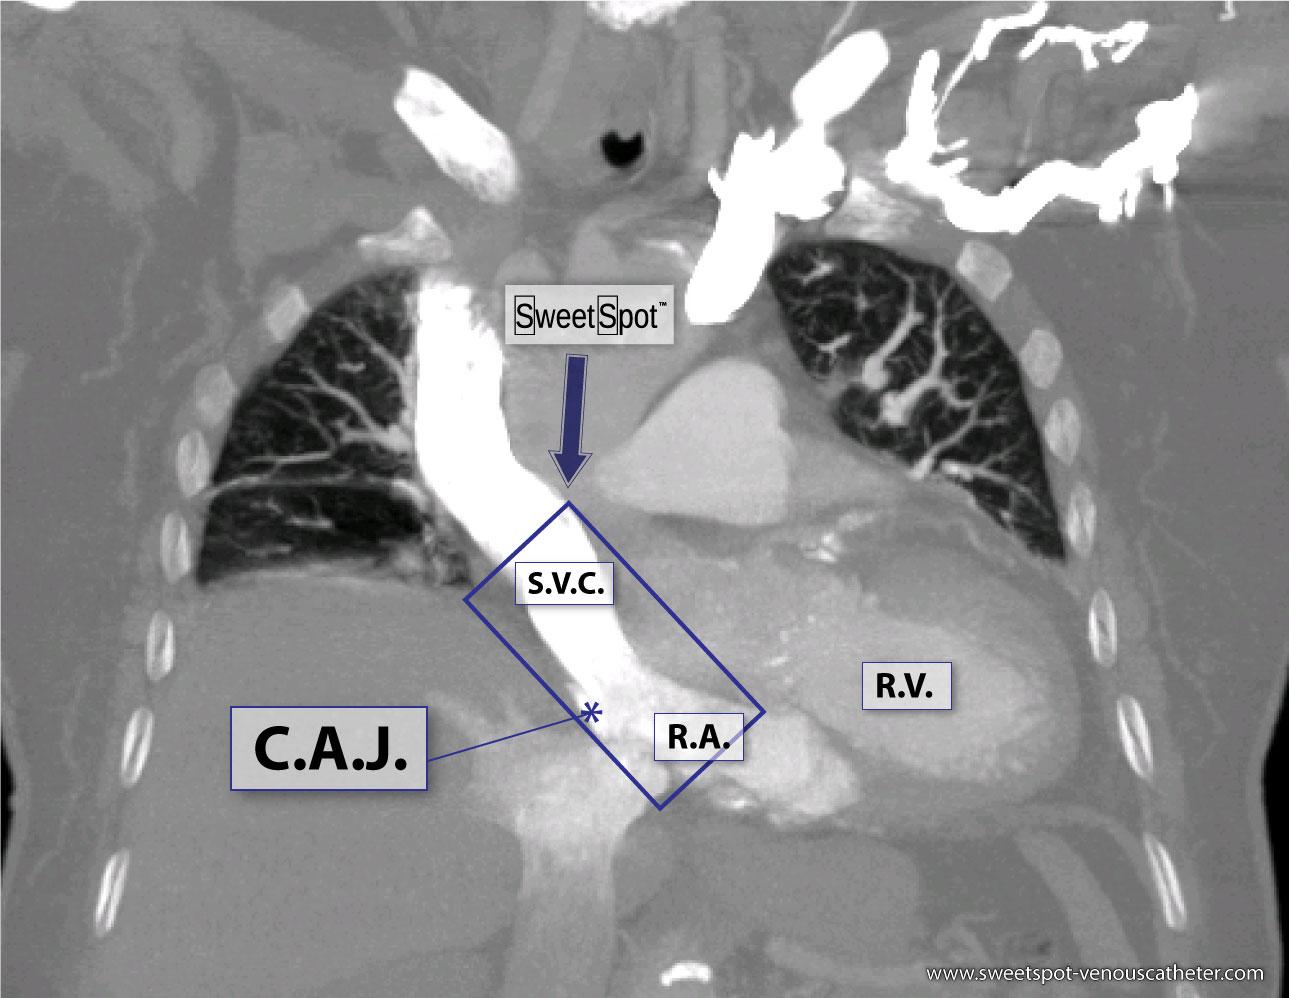

|

Figure - 04

Enhanced coronal CT reconstruction |